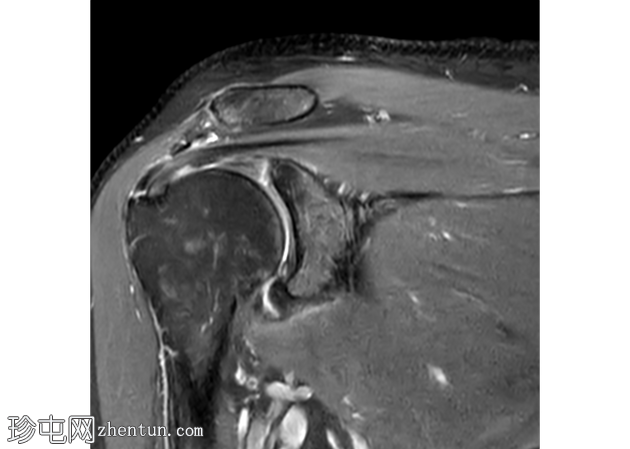

冠状面 T2

脂肪饱和度

冈上肌腱滑囊侧存在部分厚度撕裂,肌腱物质内分层延伸约2厘米,与滑囊侧分层部分厚度撕裂相符。伴有间质性肩胛下肌腱(SST)撕裂。冈上肌体积轻度减少。

冈下肌腱、小圆肌腱和肩胛下肌腱完好,无明显撕裂迹象。

冠状面可见盂唇上方T2高信号,提示SLAP损伤。SLAP损伤延伸至肱二头肌长头,矢状面清晰可见。肱二头肌长头腱正常位于肱二头肌沟内,周围积液极少。

肩胛下肌隐窝和喙突下滑囊内有少量积液。

轻度肩锁关节病,特征为轻度肥大、少量关节内积液和微量肩峰下积液。

轻度盂肱关节积液。伴有肩关节囊增厚和水肿,提示反应性关节囊炎。

未发现骨髓水肿或骨折。